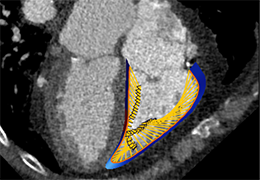

ANYTHINK 经导管主动脉瓣膜置换术分析系统